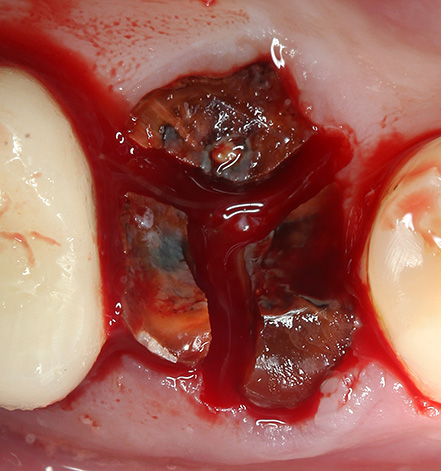

Forse ha senso dire alcune parole sulla rimozione della radice con un trapano. Il taglio delle radici con un trapano appartiene sicuramente alla categoria delle rimozioni complesse. In questo contesto, non si tratta solo di dividere le radici in 2-3 con l'obiettivo della loro sicura estrazione dall'ascensore. In alcuni casi, utilizzando un boro speciale, viene rimossa la parete ossea esterna del foro che tiene la radice.

Dopo aver creato l'accesso alla superficie esterna dell'osso, il dentista taglia la parete con un trapano e la radice che si apre dopo averla rimossa viene rimossa con una pinza o un ascensore. Il più difficile è asportare il muro di sostegno della radice nella regione dei molari inferiori (6, 7, 8), dove lo strato compatto di osso ha uno spessore significativo. Spesso, nel tempo, tali operazioni per rimuovere le radici dei denti gravemente danneggiati richiedono da 30 minuti a 3 ore e possono essere eseguite in anestesia in ospedale.

Il costo di tale rimozione può raggiungere fino a 15 mila rubli o più.